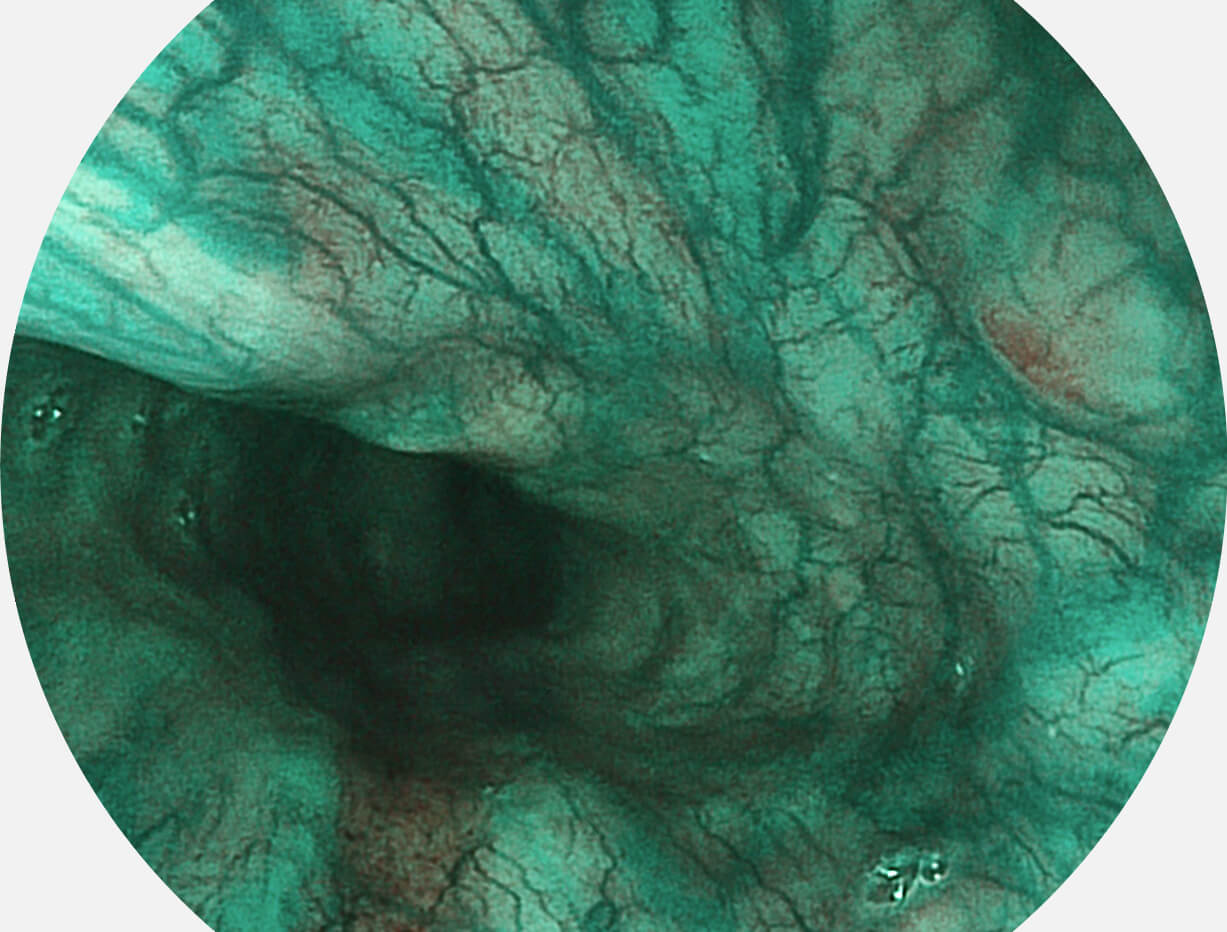

图像具有高亮度、高黏膜血管颜色对比度的特点,且不改变粘液、食物残渣、粪便的基本颜色,可在中远景下进行观察,助力消化道早期疾病的诊断。

白光图像

SFI图像